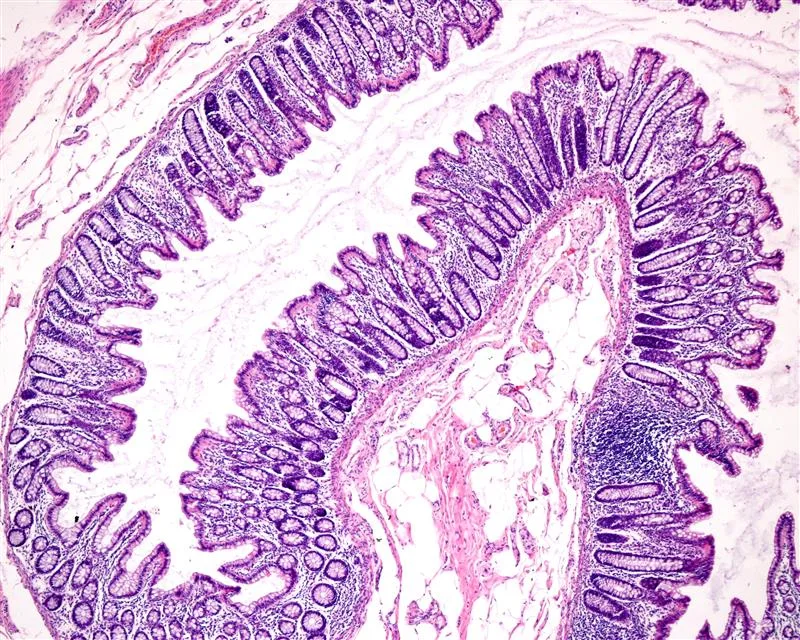

Histology reveals what symptoms, biomarkers, and endoscopy alone cannot. In GI trials, it provides direct evidence of inflammation, healing, structural changes, and treatment response — critical for demonstrating biological effect across indications such as IBD, EoE, celiac disease, and microscopic colitis.

- Inflammatory infiltrates and immune activity

- Epithelial injury, mucosal integrity, and repair

- Fibrosis, extracellular matrix remodeling, and architectural distortion